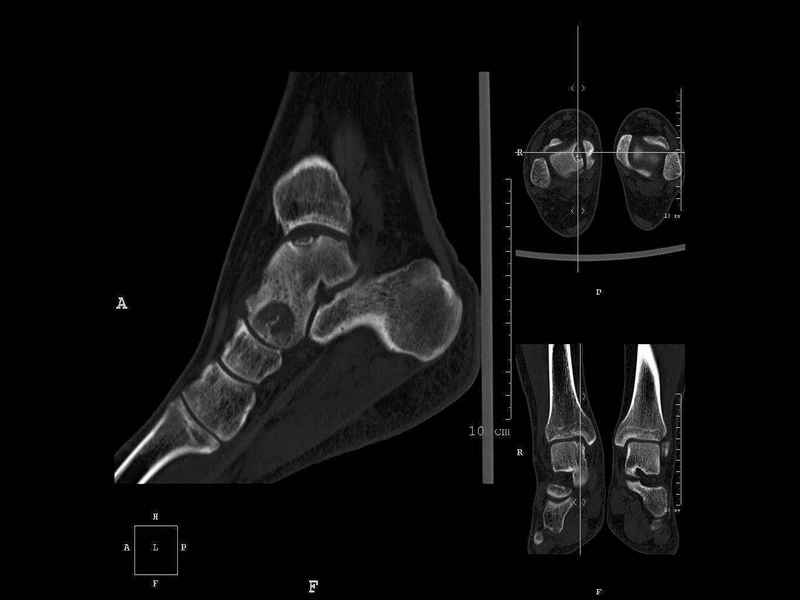

Уважаемые коллеги, обратился за помощью пациент, мужчина, 25 лет. С жалобами на болевой синдром в области голеностопного сустава и среднем отделе стопы. Травму отрицает. Со слов, болевой синдром в течении 1 года. Последние 1-1.5 мес периодически вынужден пользоваться костылями. После ограничения нагрузки боли уменьшаются.Соматически здоров. До появления болей активно занимался рукопашным боем. На СКТ картина рассекающего остеохондрита блока таранной кости, киста шейки таранной кости с признаками импрессии суставной поверхности. А также - разрастания переднего края б\берцовой кости сопровождающиеся клиникой импиджмент синдрома. Предполагаемый план лечения- удаление свободного фрагмента суставного хряща из трансмаллеолярного доступа с рассверливанием поверхности дефекта, кюретаж кисты шейки с заполнением полости биокомпозитом + дебридмент переднего отдела голеностопного сустава. Прошу высказать своё мнение, за и против, предполагаемого плана лечения. А также по возможности ответить на вопросы: 1. Есть ли необходимость в улучшении васкуляризации таранной кости (например подтаранный артродез). 2. Учитывая планируемое применение биокомпозитного цемента целесообразно ли заполнение им дефекта блока таранной кости с моделированием края суставной поверхности.